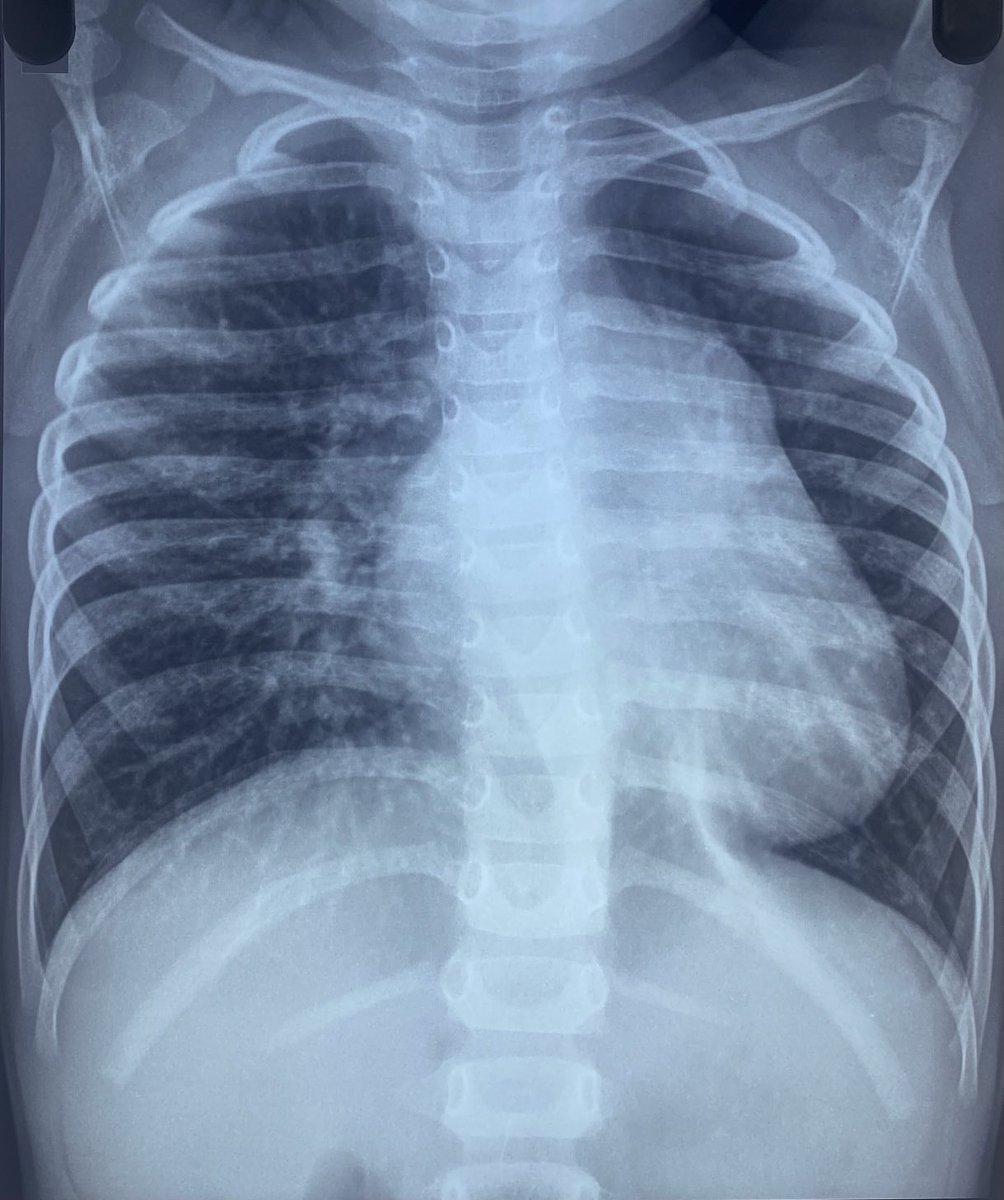

3 yr old child with H/O recurrent resp infection in infancy. Had first echo at the age of 2 years only (by an adult cardiologist) which was reported as normal. Now findings suggestive of severe PH. What lesion might have been missed in the first echo?